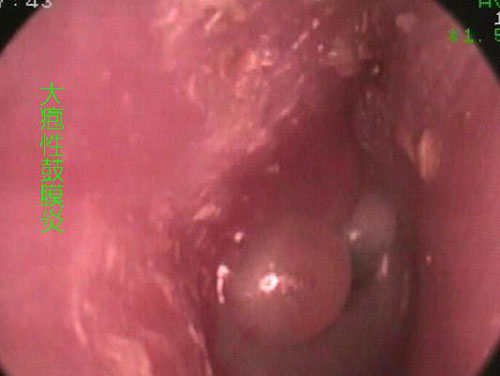

大疱性鼓膜炎又称出血性大疱性鼓膜炎,是鼓膜及其相连续外耳道皮肤的急性炎症。常发生于病毒性上呼吸道急性感染的流行期,亦可散发。好发于儿童及青年人,无性别差异,多为单侧,双侧者可同时或先后发病。

突发耳深部剧烈疼痛,伴耳闷胀感,可有轻度听力障碍。检查可见鼓膜及邻近外耳道皮肤充血,常于鼓膜后上方出现一个或多个红色或紫色血疱;有时几个血疱可融合成一大疱。血疱位于鼓膜表层内,内含血液和血浆。血疱破裂时可流出少许血性渗出液,形成薄痂而渐愈。轻者血疱内液体可被完全吸收。